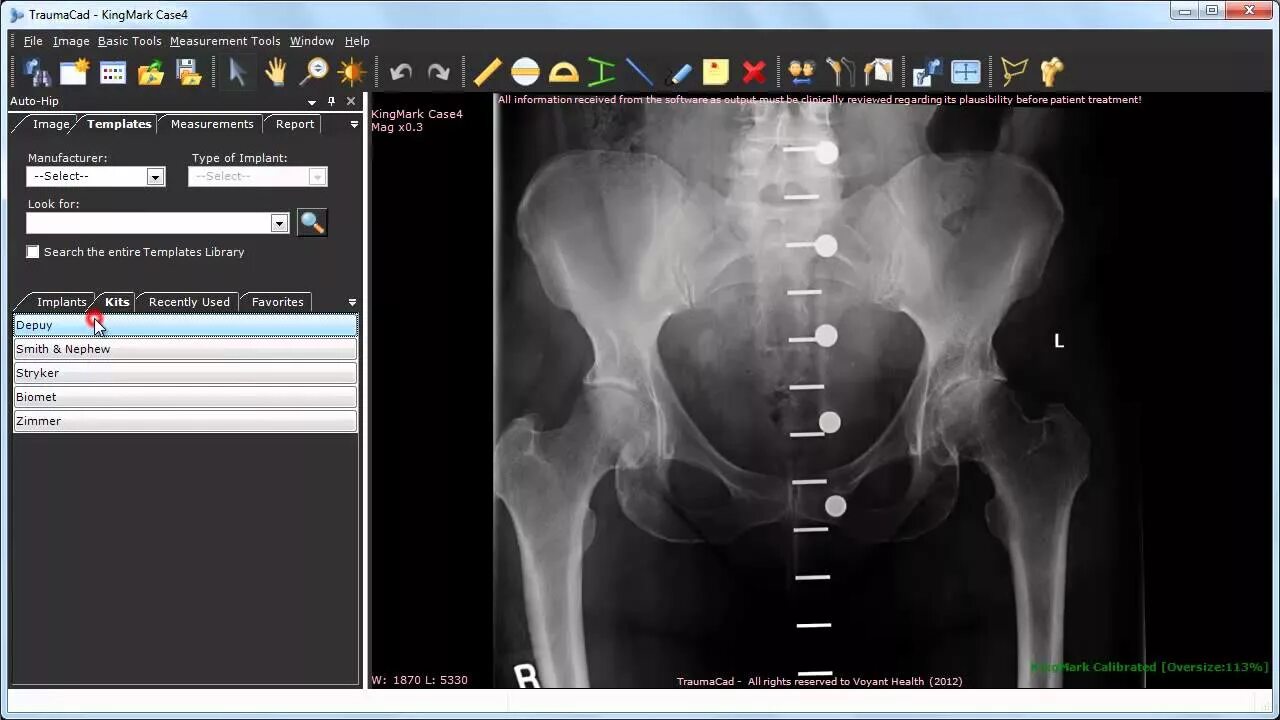

Pre operation